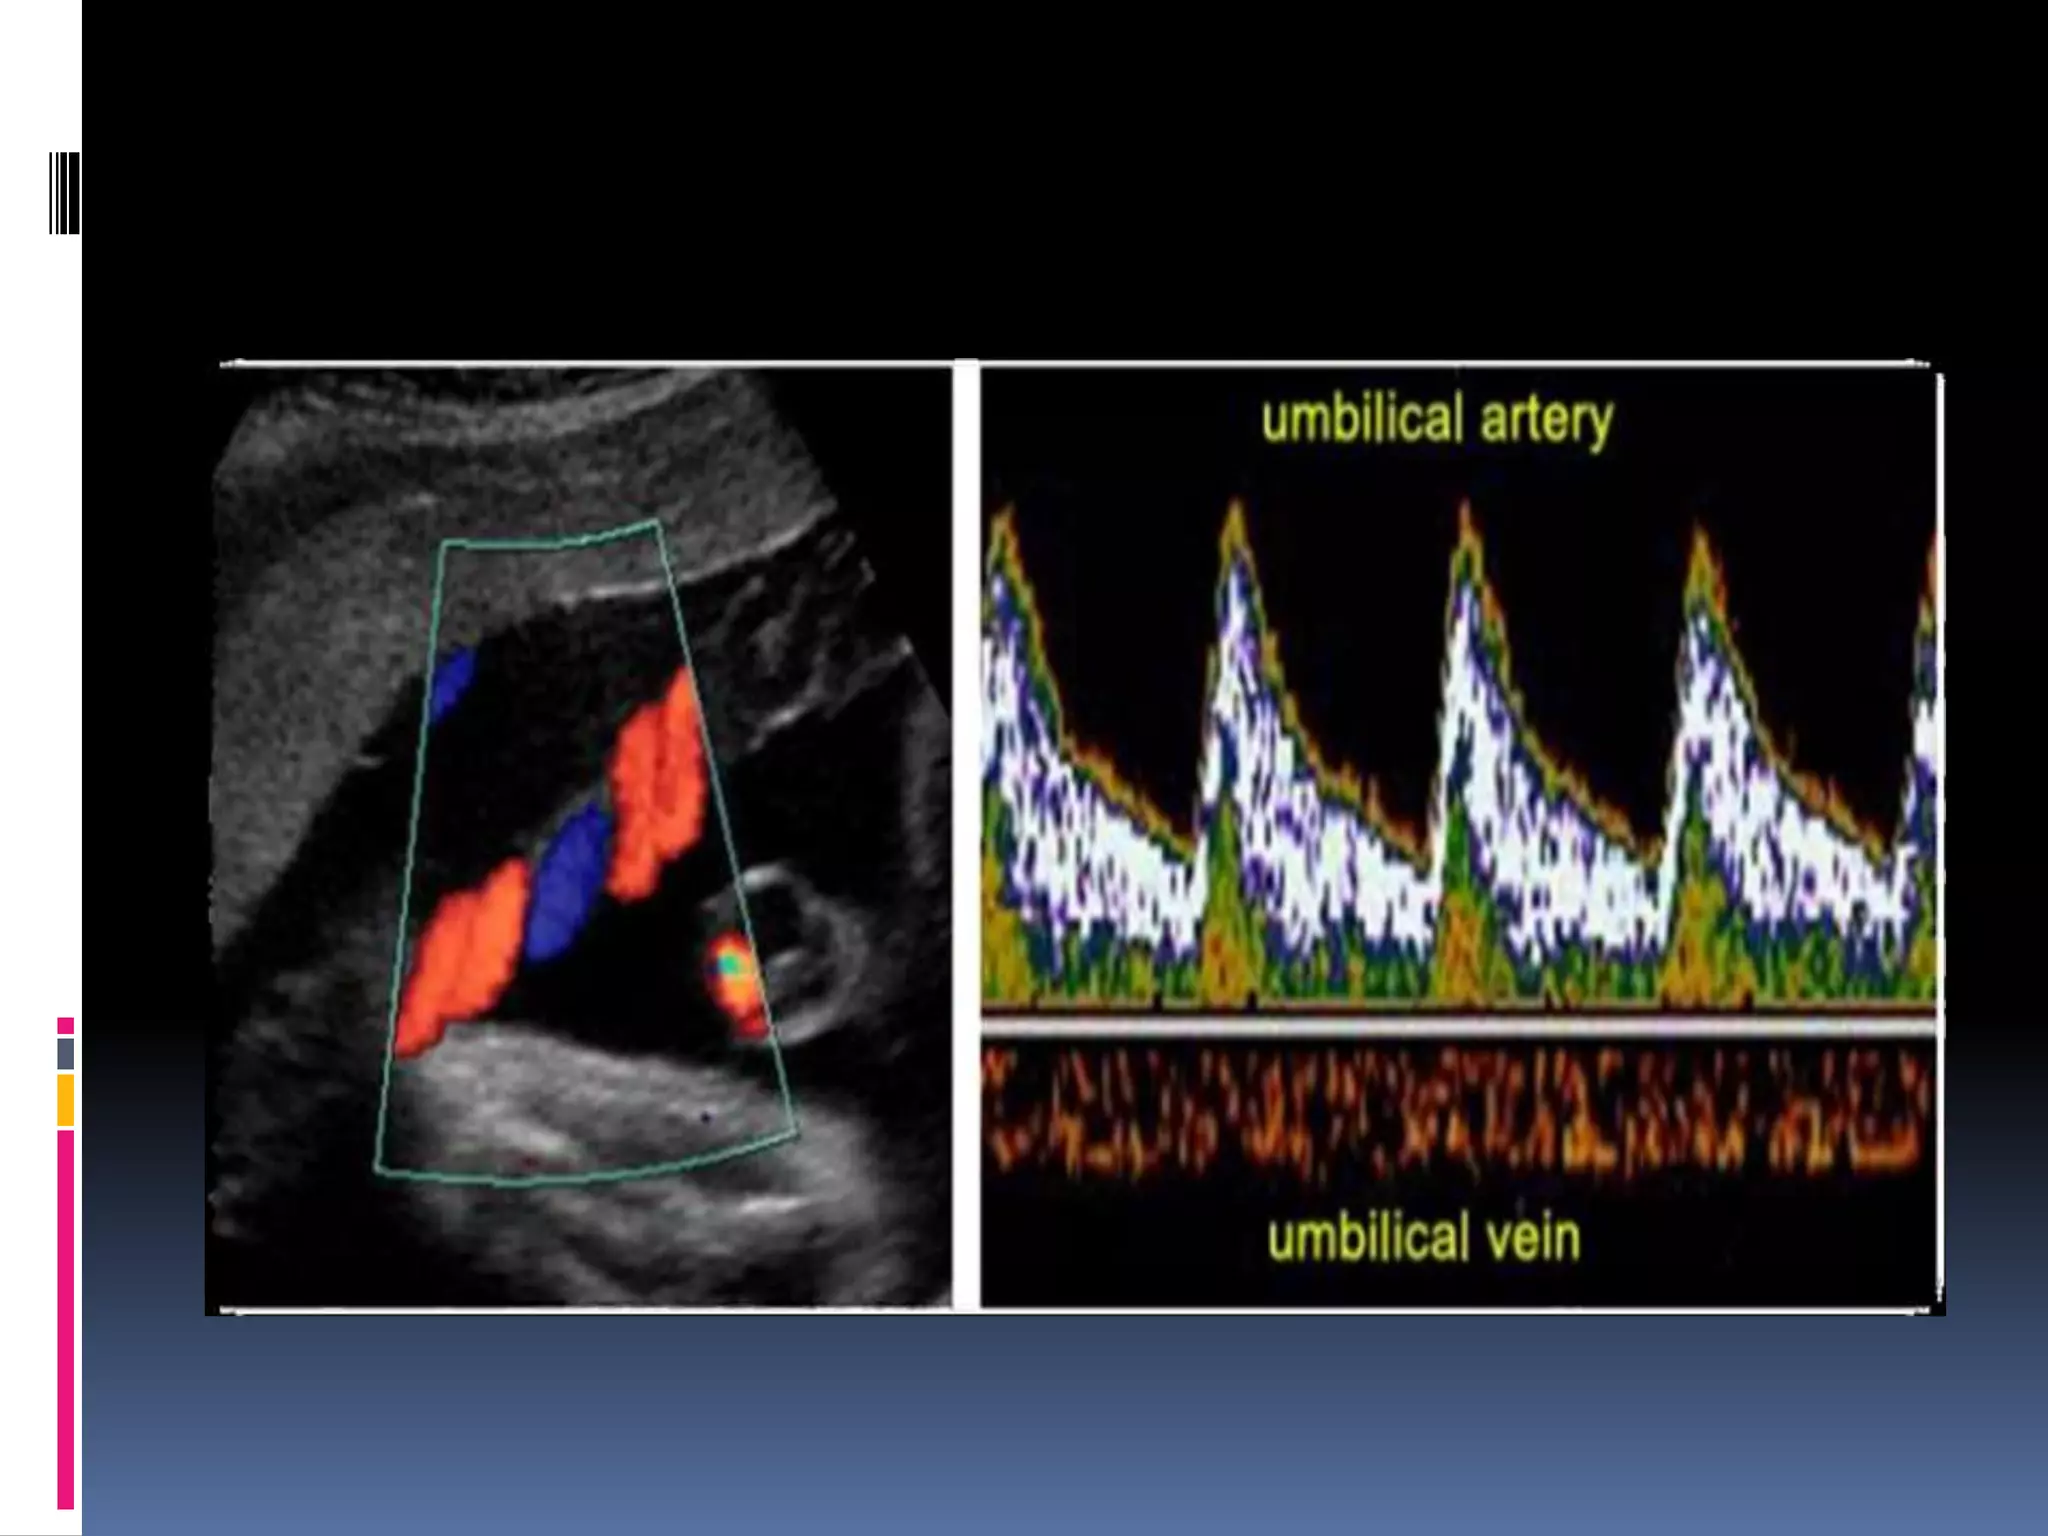

Placental side;Umbilical

arterial circulation

The umbilical arterial circulation is normally a low

impedance circulation , with an increase in the

amount of end diastolic flow with advancing

gestation . Umbilical arterial Doppler waveforms

reflect the status of the placental circulation, and

the increase in end diastolic flow that is seen

with advancing gestation is a direct result of an

increase in the number of tertiary stem villi that

takes place with placental maturation . Diseases

that obliterate small muscular arteries in

placental tertiary stem villi result in a progressive

decrease in

end-diastolic flow in the umbilical arterial Doppler waveforms

until absent, and then reverse flow during diastole is noted.

Umbilical artery Doppler

Abnormalities

Increase resistance , RI, PI, S/D

Absent diastolic flow

Reverse diastolic flow